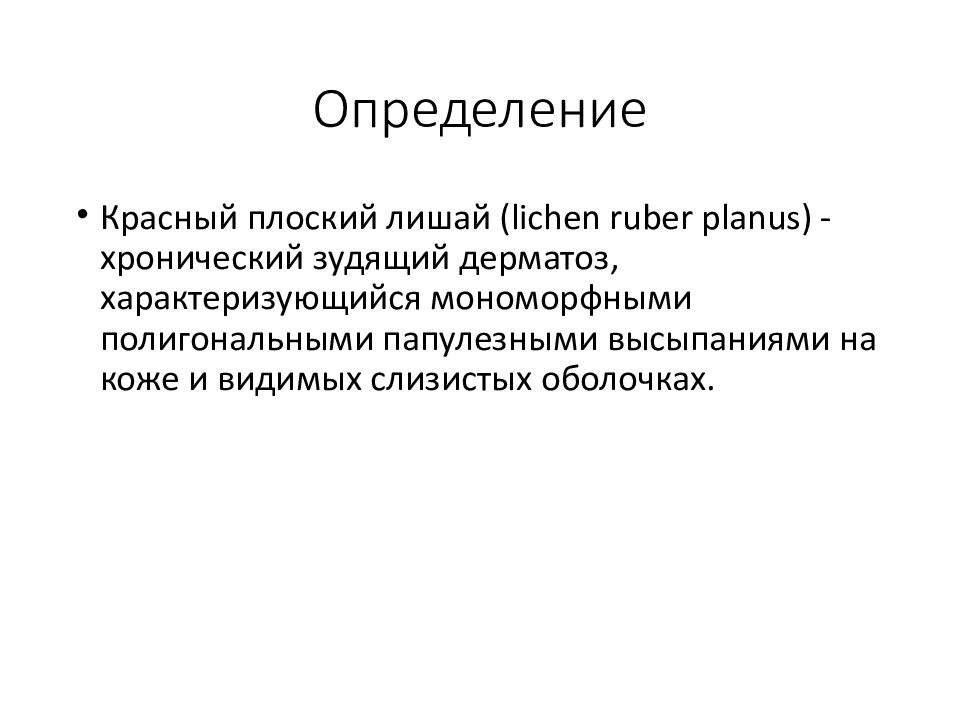

Фото Красного Плоского

Фото Красного Плоского 103 фото